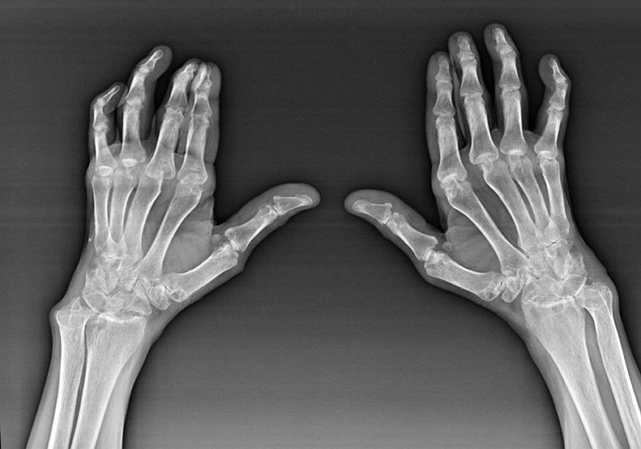

Ревматоиден артрит

Ревматоидният артрит е заболяване, при което човешката имунна система уврежда собствените тъкани на организма. С други думи, ревматоидният артрит е автоимунна патология. Това заболяване също е системно, тъй като много тъкани са засегнати от него (мускули, стави, съдове и др.) и органи (Сърце, бъбреци, бели дробове и т.н.) в тялото.

Въпреки факта, че ревматоидният артрит е системно заболяване под него, в по -голяма степен ставите страдат, докато лезията на други тъкани и органи е на заден план. При това заболяване може да се повлияят почти всички видове четки (може да се повлияят (китки, карпални пътеки, метакарпал-фаланкс, междуфаланксни стави). Лезията обикновено е симетрична (тези. Същите стави са засегнати) от двете ръце, придружени от подуване, болка в повредени стави. На сутринта, по време на повдигане от леглото, има известна скованост в засегнатите стави, която може да продължи около 1 час и след това да изчезне без следа.

Доста често с ревматичен артрит в близост до засегнатите стави на четката (По-често пиано-фалангата, междуфаланксните стави) Се появяват ревматоидни възли. Те са заоблена формация, разположена под кожата. На четката тези образувания възникват най -често на гърба. При палпация те са плътни, неактивни, безболезнени. Броят на тях може да варира.